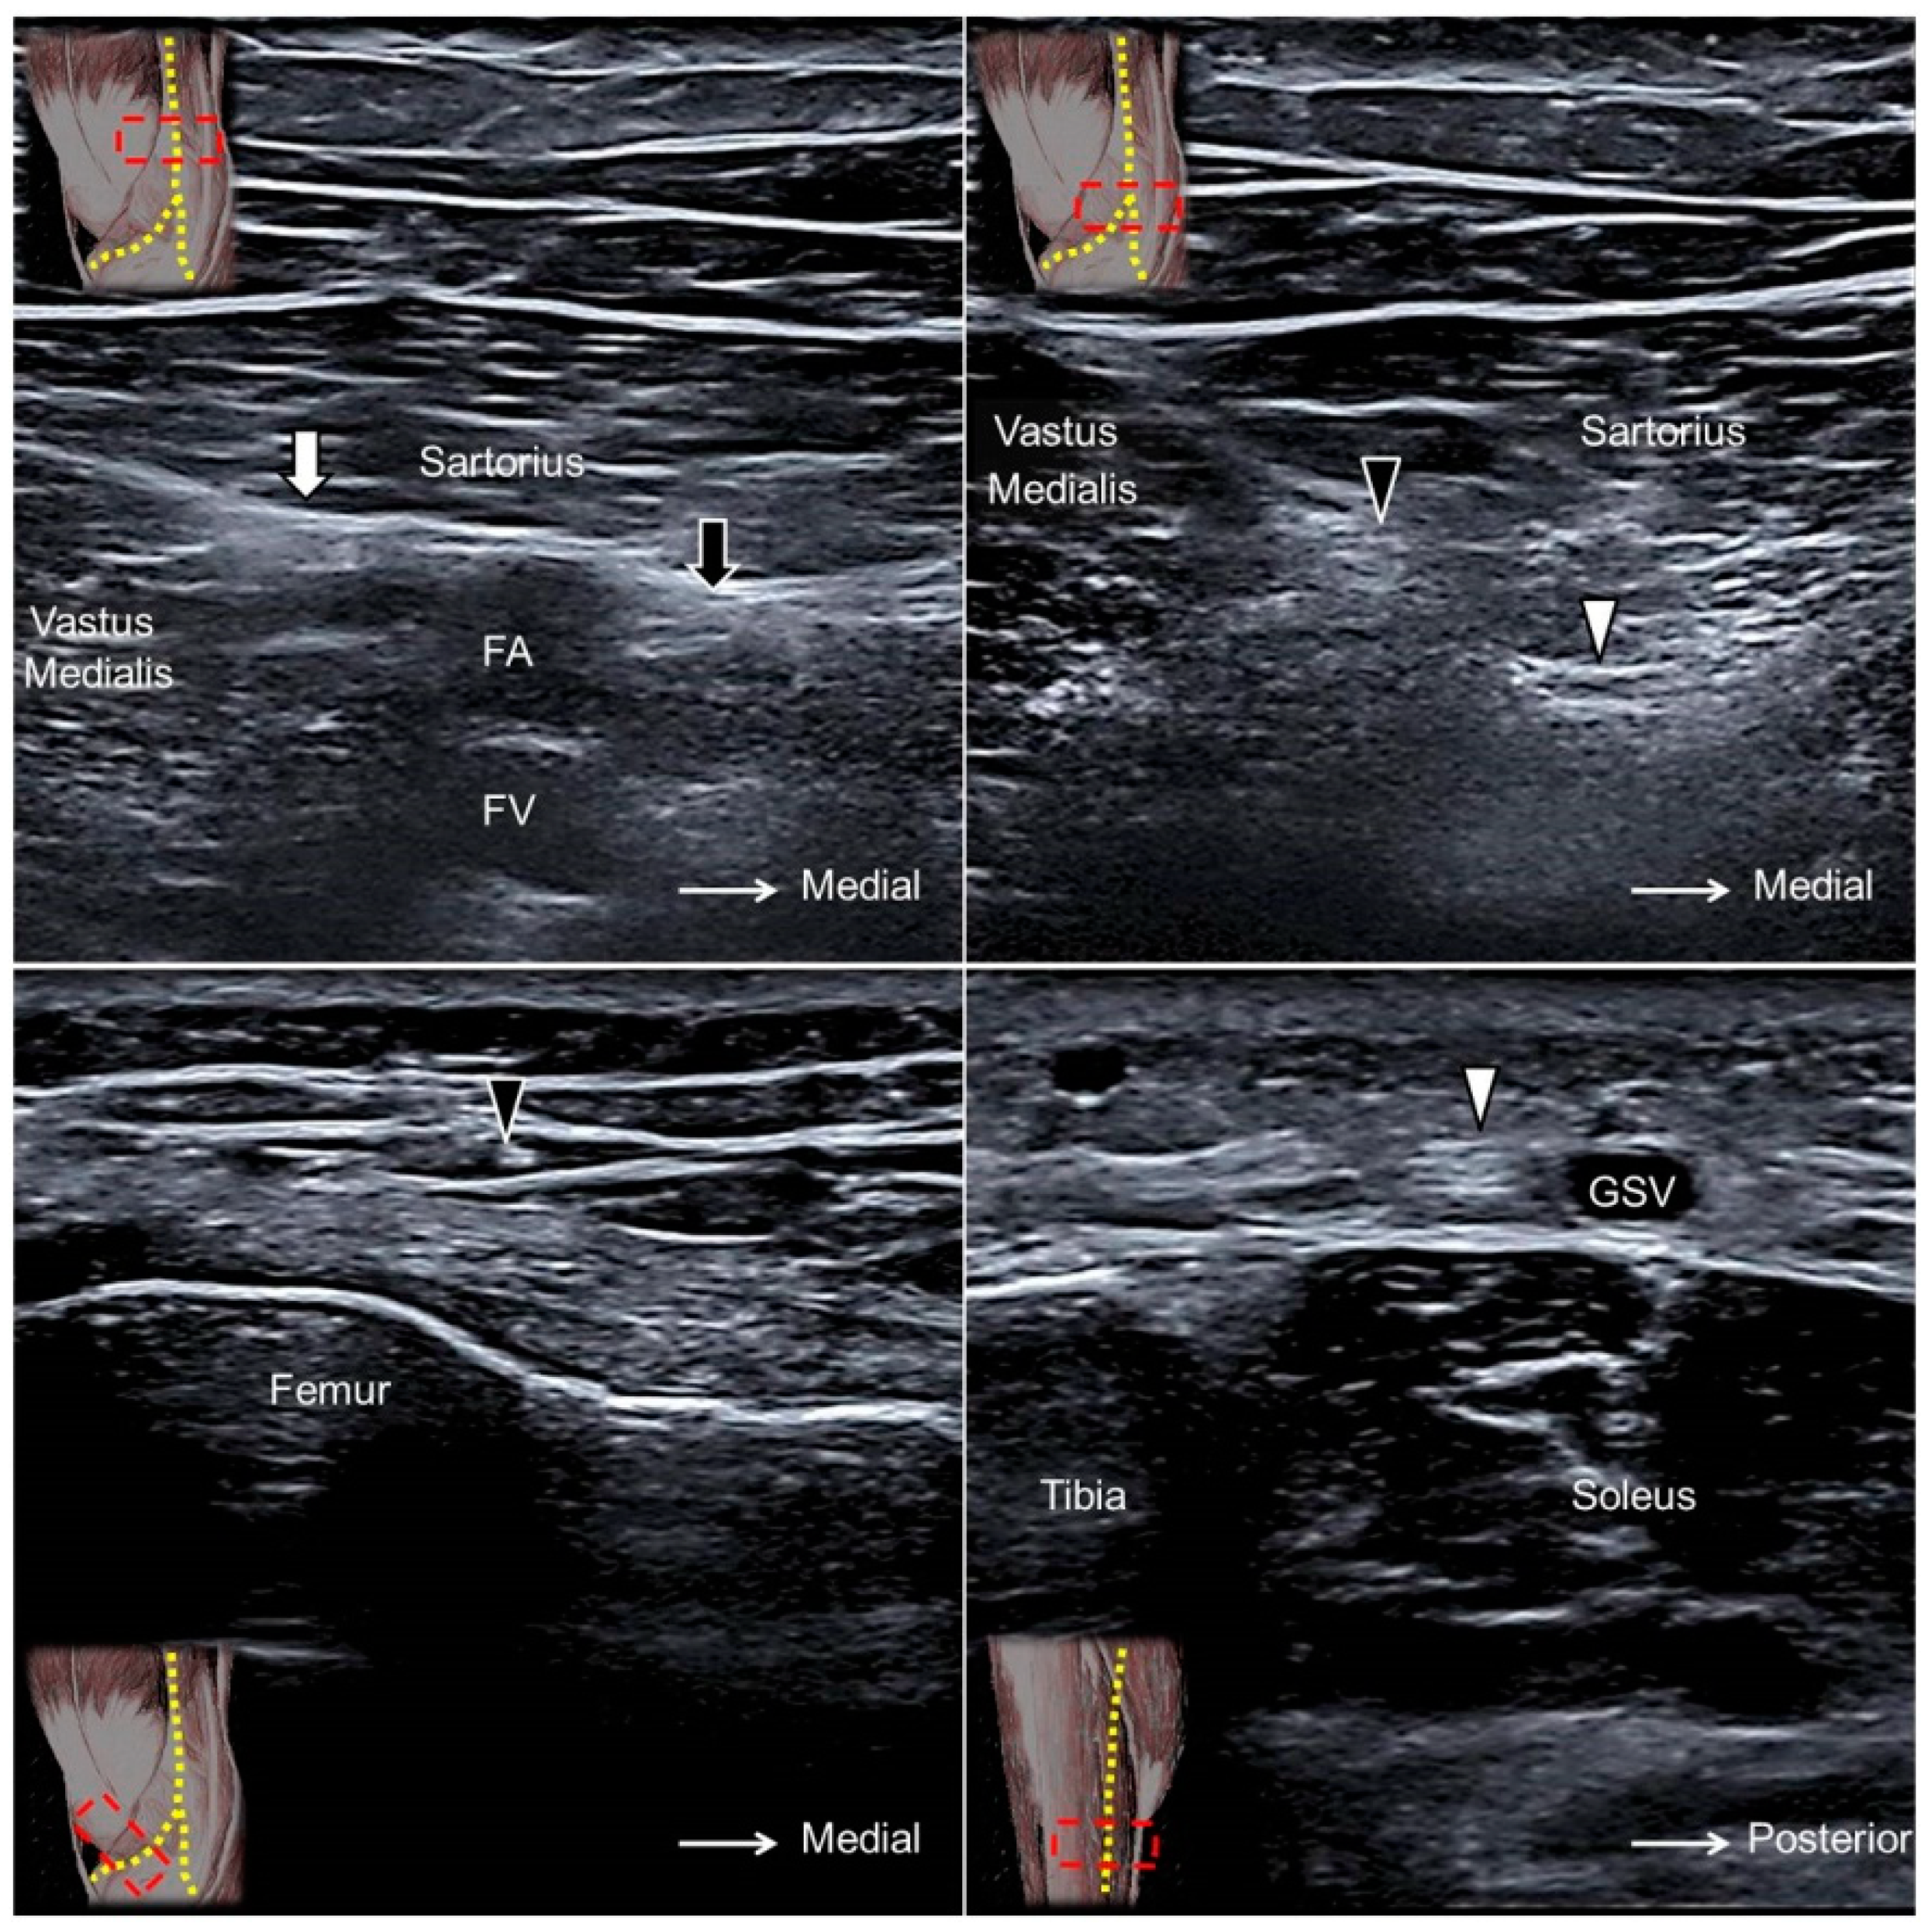

10.2. Scanning Technique

The transducer is placed horizontally at the proximal thigh to locate the femoral neurovascular bundle. The femoral nerve can be visualized lateral to the femoral artery and vein. Moving the transducer more distally, the AFCN is seen departing from the femoral nerve (Figure 9A,B) and coursing above the sartorius muscle (Figure 9C, Supplementary Video S9). It later divides into the aforementioned branches and courses in the subcutaneous layer of the anterior medial thigh [28].

13.2. Scanning Technique

The transducer is placed above the popliteal fossa where the tibial nerve is seen next to the popliteal artery. Moving the transducer distally, the tibial nerve is visualized descending under the arcade formed by the gastrocnemius muscle. At this level, the MSCN departs from the tibial nerve and surfaces along the sulcus between the two heads of the gastrocnemius muscle (Figure 11D, Supplementary Video S12).

Placing the transducer at the lateral border of the popliteal fossa, the common peroneal nerve is found inside the gap interposed between the biceps femoris and lateral gastrocnemius muscles. Relocating the transducer caudally, the LSCN can be seen branching from the medial aspect of the common peroneal nerve (Supplementary Video S13). The LSCN descends along the lateral head of gastrocnemius muscle and gives off a communicating branch to connect to the MSCN at the mid-calf level to form the sural nerve.

The sural nerve descends with the small saphenous vein and courses between the Achilles tendon and peroneus muscles at the distal leg (Figure 11E). The nerve gives off the lateral calcaneal branch at the level of the superior peroneal retinaculum, whereas the terminal branch courses more distally along the dorsal lateral aspect of the foot (Figure 11F, Supplementary Video S14) [33].

The transducer is placed in the horizontal plane at the proximal medial thigh to locate the adductor canal. The canal is bordered by the sartorius muscle superficially, the vastus medialis muscle laterally, and the adductor longus muscle deeply. The saphenous nerve can be seen as a hyperechoic oval-shaped structure inside the canal with the femoral artery and vein (Figure 13A). Moving the transducer more distally, the saphenous nerve will be seen exiting the adductor canal together with the descending genicular artery. Near the exit of the adductor canal, the saphenous nerve gives off the infrapatellar branch, emerging through the fascial plane interposed between the vastus medialis and sartorius muscles to the subcutaneous layer (Figure 13B,C, Supplementary Video S15). The sartorial branch descends and surfaces to the subcutaneous layer at the posterior aspect of the sartorius muscle. The sartorial branch courses next to the greater saphenous vein at the anterior medial aspect of the leg and ankle (Figure 13D, Supplementary Video S15) [35].

Figure 9. The anterior femoral cutaneous nerve (black arrowhead) at the femoral triangle in its short (A) and long (B) axes and at the mid-thigh level (C). The posterior femoral cutaneous nerve (white arrowhead) at the gluteal fold in its short axis (D) and long axis (E) and at the ischiofemoral interval (F). FN, femoral nerve; FA, femoral artery; GMA, gluteus maximus muscle; CT, hamstring conjoint tendon; ST, semitendinosus tendon; SN, sciatic nerve; QF, quadratus femoris muscle.

Figure 11. The lateral femoral cutaneous nerve (yellow arrowhead) at the level of the anterior iliac fossa (A), anterior superior iliac spine (B), and the fat compartment interposed between the sartorius and tensor fasciae latae muscles (C). The medial sural cutaneous nerve (white arrowhead) (D) and the lateral sural cutaneous nerve (black arrowhead) of the posterior leg, the sural nerve (black arrow) at the level of the distal leg (E), and the lateral foot (F). Black dashed line, fascia lata; white dashed line, fascia iliaca; MG, medial gastrocnemius; LG, lateral gastrocnemius; PL, peroneus longus; PB, peroneus brevis; CFL, calcaneofibular ligament; white arrow, lateral calcaneal branch of the sural nerve.

Figure 13. The saphenous nerve (black arrow) proximal to the exit of the adductor canal (A). The infrapatellar (black arrowhead) and sartorial (white arrowhead) branches of the saphenous nerve at the exit of the adductor canal (B). The infrapatellar branch on the distal femur (C) and the sartorial branch on the distal tibia (D). White arrow, nerve to the vastus medialis muscle; FA, femoral artery; FV, femoral vein; GSV, great saphenous vein.